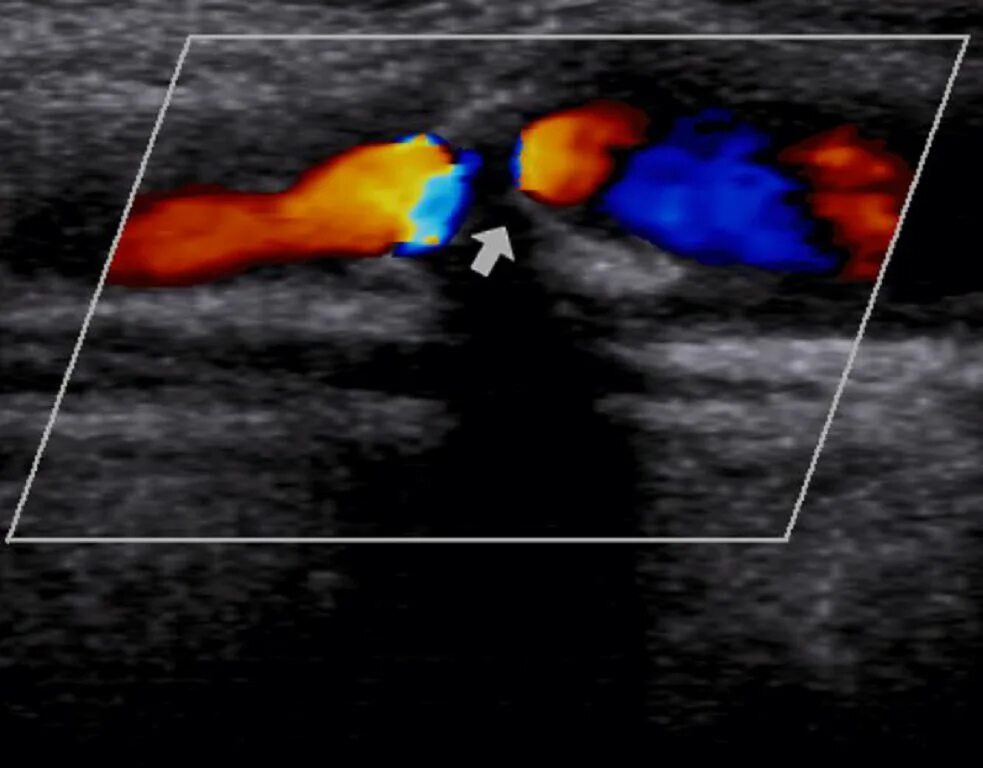

Атеросклероз на узи